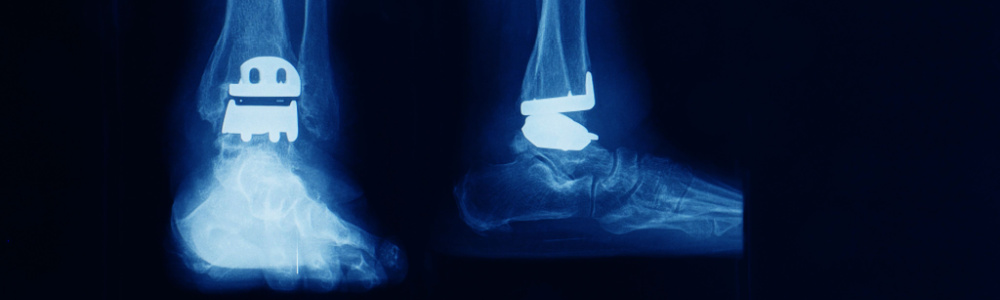

Exactech’s polyethylene ankle replacement inserts were recalled because of the same lack of a second barrier, leading to oxidation and premature failure. After several surgeons and patients reported the early wearing down the Food and Drug Administration to institute a Class 2 Device Recall. If your ankle replacement wears down prematurely, it can not only lead to further surgeries or an entirely new ankle replacement, but immense pain, not to mention the emotional and economic damages you incur.

You should immediately call your doctor to set up an appointment. The doctor will go over any symptoms you are having, and take x-rays to verify the condition of the ankle, knee or hip replacement. If your liner or insert has not yet resulted in any damages, your doctor will know how to best move forward.